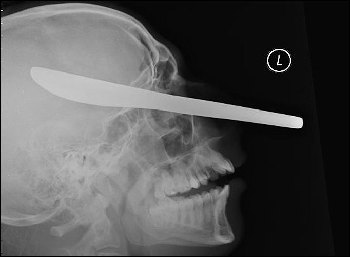

一把用來抹黃油的刀就這樣插在了受害人邁克爾的頭部。

當醫生向邁克爾展示這張恐怖的頭部X光片時,他不敢相信自己的眼睛——一把用來抹黃油的刀從他的左側臉頰穿過,直達他右側的頭蓋骨,距離他的大腦只有1英寸(約2.5厘米)。

在庭上,法官尤伊斯特說:“我看過那張X光片,我只能用惡心和震驚來形容看到照片的感覺。我不能理解一個人怎么可以如此惡毒,做出這樣的事情。你(馬克)對社會沒有任何貢獻,你必須一輩子都處于警方監管之下。”